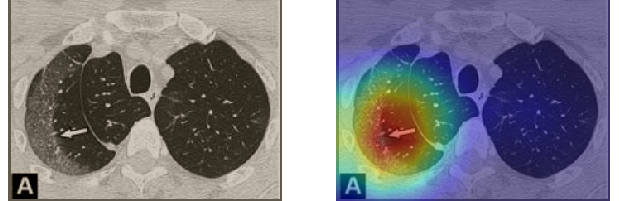

In order to make our models more transparent and provide detailed visual analysis, we present the Grad-CAM localization maps obtained by different models. We consider CT images with COVID-19 abnormalities from the test set of each dataset and highlight the important regions considered for the prediction. For the SARS-CoV-2 dataset we use the Inception V3 model. Figure 13 shows the original CT images and their localization maps. Our model is capable to detect regions that show abnormalities in the CT scans.

In a similar way, we consider classifying the test CT scans from the COVID-19 dataset by the DenseNet169 model and highlight the important regions considered for predictions. We present the original CT images and their localization maps in Figure 13. We can also see that our model is capable to detect the COVID-19 related regions as marked (small square in some images) by expert radiologists.

A wide variety of typical and atypical CT abnormalities have been reported for COVID-19 patients in various studies [58, 59]. So, we tested our models on external CT images extracted from these two publications as they feature typical findings of COVID-19 pneumonia marked by specialists. In order to make sure that not any of the extracted images are unintentionally included in our datasets, specifically the COVID19-CT dataset, we use the model trained on the SARS-CoV-2 dataset. First, the InceptionV3 model is employed to classify the extracted CT images. The model is able to correctly classify the given CT images as COVID-19. Second, in order to interpret the model’s generalization capabilities, we apply the Grad-CAM technique to visualize the regions of abnormalities that are considered. By assessing the different CT images in Figure 15, we can see that the model accurately localizes the disease-related regions. Even more interesting is the fact that the model ignores any specific marks in the images like letters and only localizes the COVID-19 related regions. These visual explanations show the success of our models to learn relevant, generic visual features related to COVID-19 and are capable to correctly classify CT images outside the datasets on which they are trained.